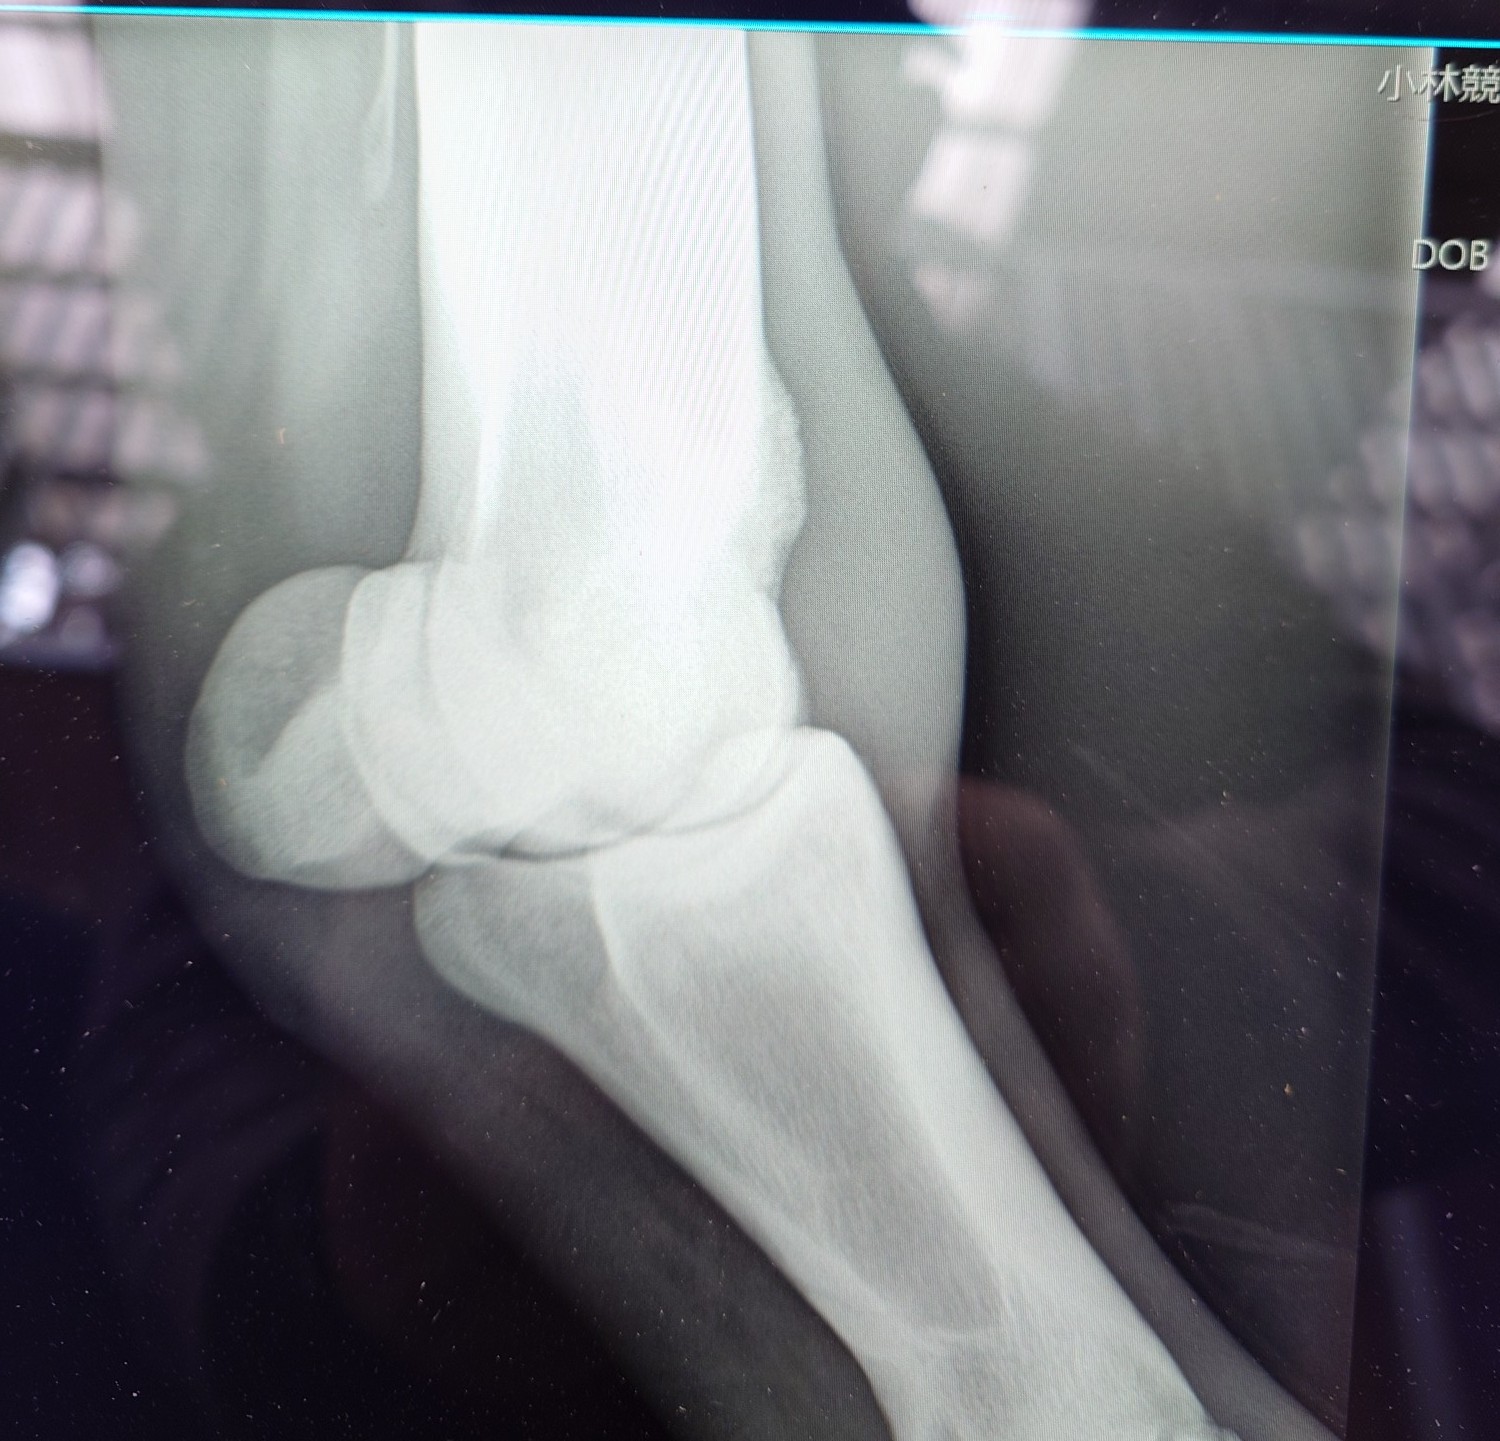

2012年にケンタッキーダービーを制した父アイルハヴアナザー産駒はアナザートゥルース(セン12歳)、オメガレインボー(牡10歳)他、タフなダート馬が多い。本馬は2歳時の6月に大井競馬場で新馬勝ちし、ハイセイコー記念6着後、3連勝で雲取賞へ臨み3着。羽田盃、東京ダービー後、休養して秋はA2B1クラスで出走しましたが惨敗が続いたため4歳時の2月28日に去勢。その後も結果を出せませんでしたが、5歳の8月にライアンクアトロ騎手が跨って快勝。そこからコンスタントに出走してA2(JRA交流2勝)クラスの特別戦で4勝を挙げました。8歳になった今年の3月の川崎戦で8着後、左前脚の球節が腫れてしまい、レントゲン検査で骨膜を発症していることが判明しました。剥がれかかっており、獣医師から全治3~4カ月と診断されたため現役を断念、引退することになりました。